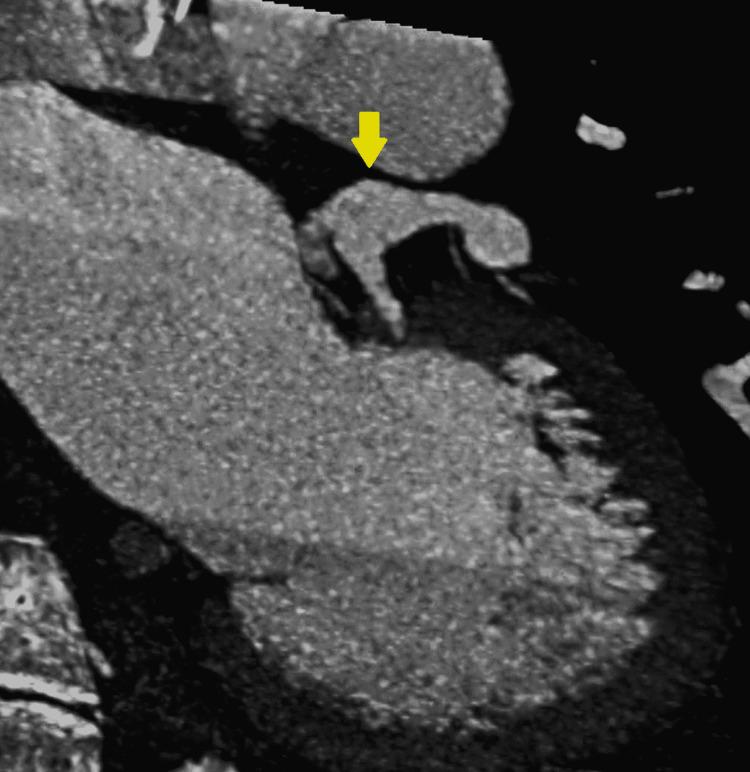

Aneurysm of the coronary artery is an uncommon condition that is usually found incidentally. The left coronary aneurysm is the least common. We report the case of a young patient with a history of vasculitis who was found to have a left fusiform coronary aneurysm. This is a 20-year-old female who has a history of polyarteritis nodosa and who came due to shortness of breath associated with chest discomfort. The physical exam was only relevant for multiple joint pains and tenderness. An echocardiogram showed a possible coronary aneurysm that was confirmed on the angio-tomography. The patient was discharged without complications. The left main coronary artery aneurysm is a rare condition and the least common of the coronary aneurysms. There is no established guideline for screening and therapy of these aneurysms, but invasive methods are not a preferred method for follow-up on this condition.

冠状动脉瘤是一种罕见的病症,通常是偶然发现的。左冠状动脉瘤最为少见。我们报告一例有血管炎病史的年轻患者,该患者被发现患有左冠状动脉梭形动脉瘤。这是一名20岁女性,有结节性多动脉炎病史,因呼吸急促伴胸部不适前来就诊。体格检查仅发现多处关节疼痛和压痛。超声心动图显示可能存在冠状动脉瘤,血管断层扫描证实了这一情况。患者出院时无并发症。左冠状动脉主干动脉瘤是一种罕见病症,也是冠状动脉瘤中最不常见的。目前尚无针对这些动脉瘤筛查和治疗的既定指南,但侵入性方法并非对该病症进行随访的首选方法。